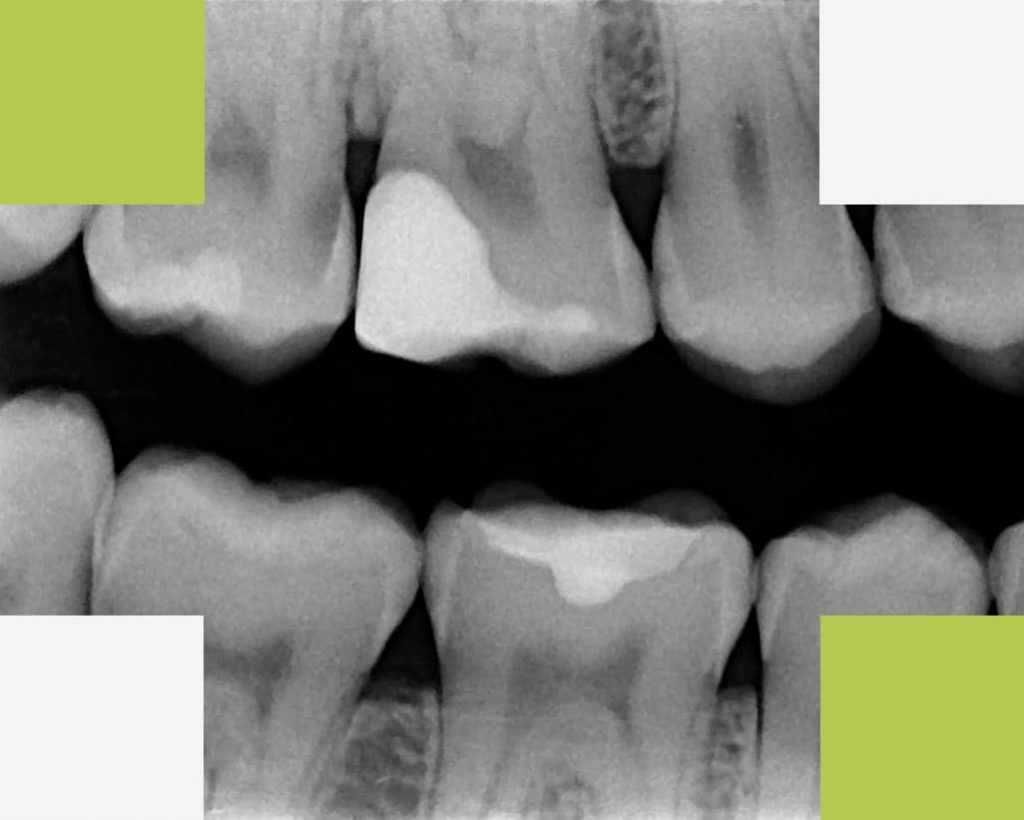

3. Radiografia digitală bite-wing

Radiografia bitewing se realizează pentru a observa punctele sau suprafețele de contact dintre coroanele dinților posteriori adiacenți sau conturul osului alveolar la acest nivel. Sunt surprinse atât coroanele dinților superiori cât și a celor inferiori pe același film. Scopul radiografiei este de a depista cariile interdentare sau pe cele care se formează sub obturații sau lucrări.